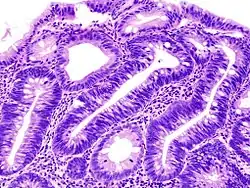

Ein Adenom (von altgriechisch ἀδήν adēn „Drüse“ und -ωμα -ōma als Wortteil mit der Bedeutung von „Geschwulst“, „Erguss“) ist eine gutartige Geschwulst aus Schleimhaut oder Drüsengewebe und kann generell jedes Organ betreffen.

Am häufigsten kommt das Adenom jedoch im Magen-Darm-Trakt als Polyp vor. Weitere häufige Formen betreffen die Schilddrüse, die Nebennieren und die Eierstöcke. In der weiblichen Brust beziehungsweise Milchdrüse tritt es meist als Fibroadenom unter Beteiligung von Drüsen- und Bindegewebe auf.